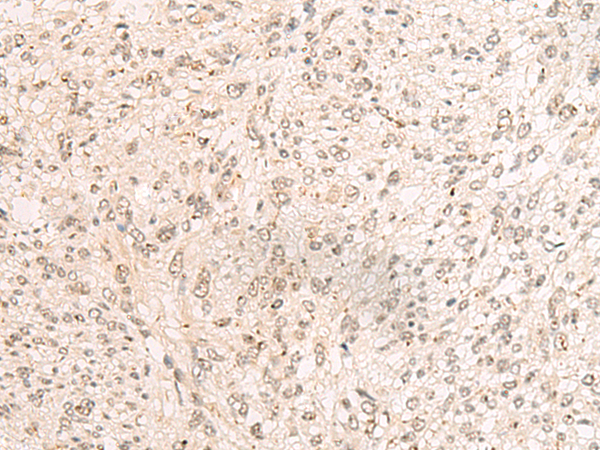

分类: 科研抗体货号: P09924别名: PD2; F23149_1应用: IHC反应种属: Human, Mouse, Rat